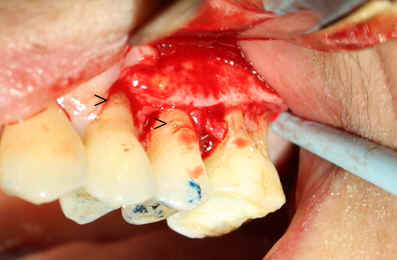

| 图五 牙周手术前左上6号牙颊侧根分叉暴露(箭头) | 图六 牙周手术前左上6号牙舌侧牙龈退缩(箭头) |

检查:6号牙颊舌侧牙龈退缩(图五,图六)